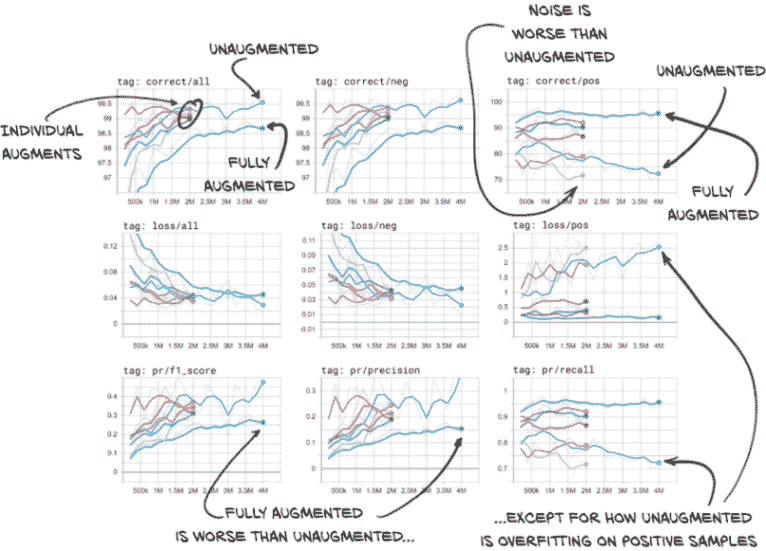

如果让所有内容运行到完成,您的 TensorBoard 应该有类似图 12.22 所示的数据。我们将取消选择除验证数据之外的所有内容,以减少混乱。当您实时查看数据时,还可以更改平滑值,这有助于澄清趋势线。快速查看一下图,然后我们将详细介绍它。

图 12.22 用各种增强方案训练的网络在验证集上正确分类的百分比、损失、F1 分数、精度和召回率

在左上角的图表中第一件要注意的事情(“标签:正确/全部”)是各个增强类型有些混乱。我们的未增强和完全增强的运行位于该混乱的两侧。这意味着当结合时,我们的增强效果超过了其各部分之和。还有一个有趣的地方是,我们的完全增强运行得到了更多错误答案。虽然这通常是不好的,但如果我们看一下右侧的图像列(重点是我们实际关心的正候选样本–那些真正的结节),我们会发现我们的完全增强模型在查找正候选样本方面要好得多。完全增强模型的召回率很高!它也更不容易过拟合。正如我们之前看到的,我们的未增强模型随着时间的推移变得更糟。

值得注意的一点是,噪声增强模型在识别结节方面比未增强模型更差。如果我们记得我们说过噪声会让模型的工作变得更困难,这就说得通了。

在实时数据中看到的另一个有趣的事情(在这里有点混乱)是,旋转增强模型在召回方面几乎与完全增强模型一样好,并且在精度上有很大提高。由于我们的 F1 分数受精度限制(由于负样本数量较高),旋转增强模型的 F1 分数也更高。

未来我们将继续使用完全增强的模型,因为我们的用例需要高召回率。F1 分数仍将用于确定哪个时期保存为最佳。在实际项目中,我们可能希望花费额外的时间来调查不同的增强类型和参数值组合是否能产生更好的结果。